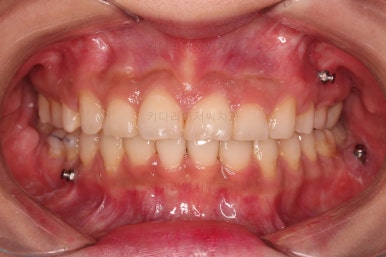

1. 초진

연산동교정치과 초진 시 입안의 모습입니다.

얼핏 앞에서 봤을 때 치열이 나쁘지 않아 보이는데요.

대신 자세히 살펴보면 윗니 양쪽 송곳니가 덧니처럼 볼록 튀어나와 있고요.

아랫니 어금니가 하나 없어서 주위 치아들이 해당 위치로 쓰러진 상태였습니다.

그리고 양쪽의 교합이 톱니바퀴처럼 맞물려 있는 것 같지만 톱니바퀴가 한 칸씩 밀려서 맞물려 있는 부정교합이 있는 상태였습니다.